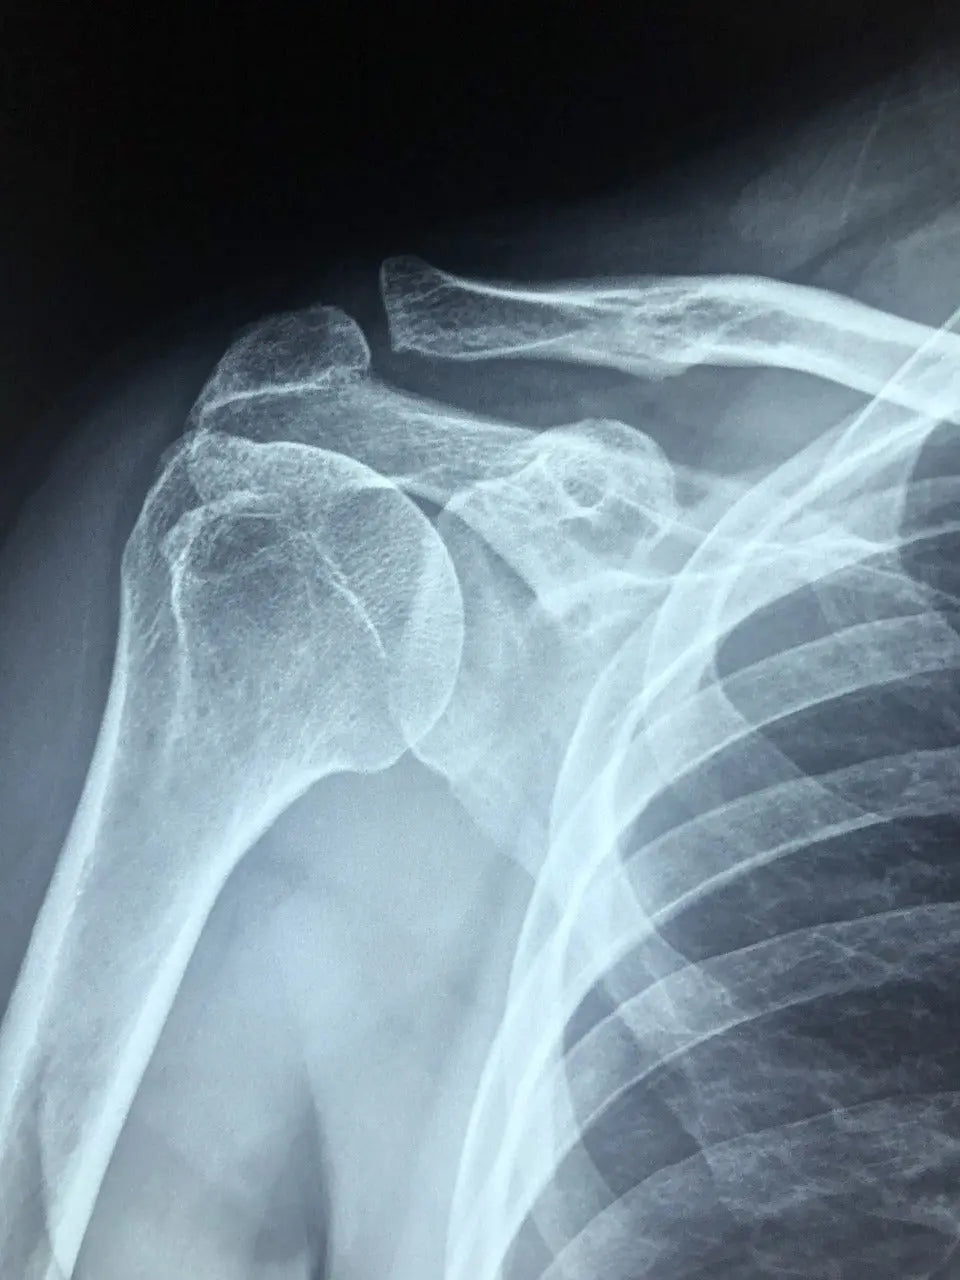

3. Déchirure de la coiffe des rotateurs

Quand un ou plusieurs tendons/muscles qui stabilisent ton épaule lâchent partiellement ou complètement. Douleur forte + perte de mobilité.

4. Syndrome de conflit sous-acromial

Quand les tendons frottent sous l’acromion (os de l’omoplate) => douleur à l’élévation du bras.